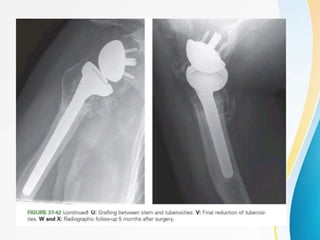

FIXATION OF PHF USING PHILOS(3 PART

AND 4 PART)

-Principles of fixation

-Approaches

-Exposures

-Surgical steps

-Intraop image intensifier(c-arm)

STEP 4 :

• if needed , a lag screw can be inserted into

lesser tuberosity .

• additional shaft screws are inserted (bicortical

screws)

• Rotator cuff tendon sutures are placed through

the suture holes and secured { ↑ stability }